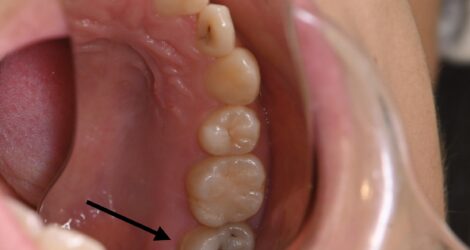

みなさんこんにちは、歯科衛生士の舘山です😃 今回は右上7、MTAセメントの紹介になります。 痛みがなく、症状もなく、大きく虫歯になっていました🦷 【処置前】 【処置動画】 https://youtu.be/gi7KGqB-ijA 【治療金額】 ¥55,000/1回 ※別途補綴代がかかります 【担当医】 DR北野